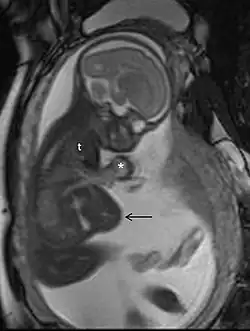

Common uses

MRI is commonly used in pregnant women with acute abdominal pain and/or pelvic pain, or in suspected neurological disorders, placental diseases, tumors, infections, and/or cardiovascular diseases.[3] Appropriate use criteria by the American College of Radiology give a rating of ≥7 (usually appropriate) for non-contrast MRI for the following conditions: